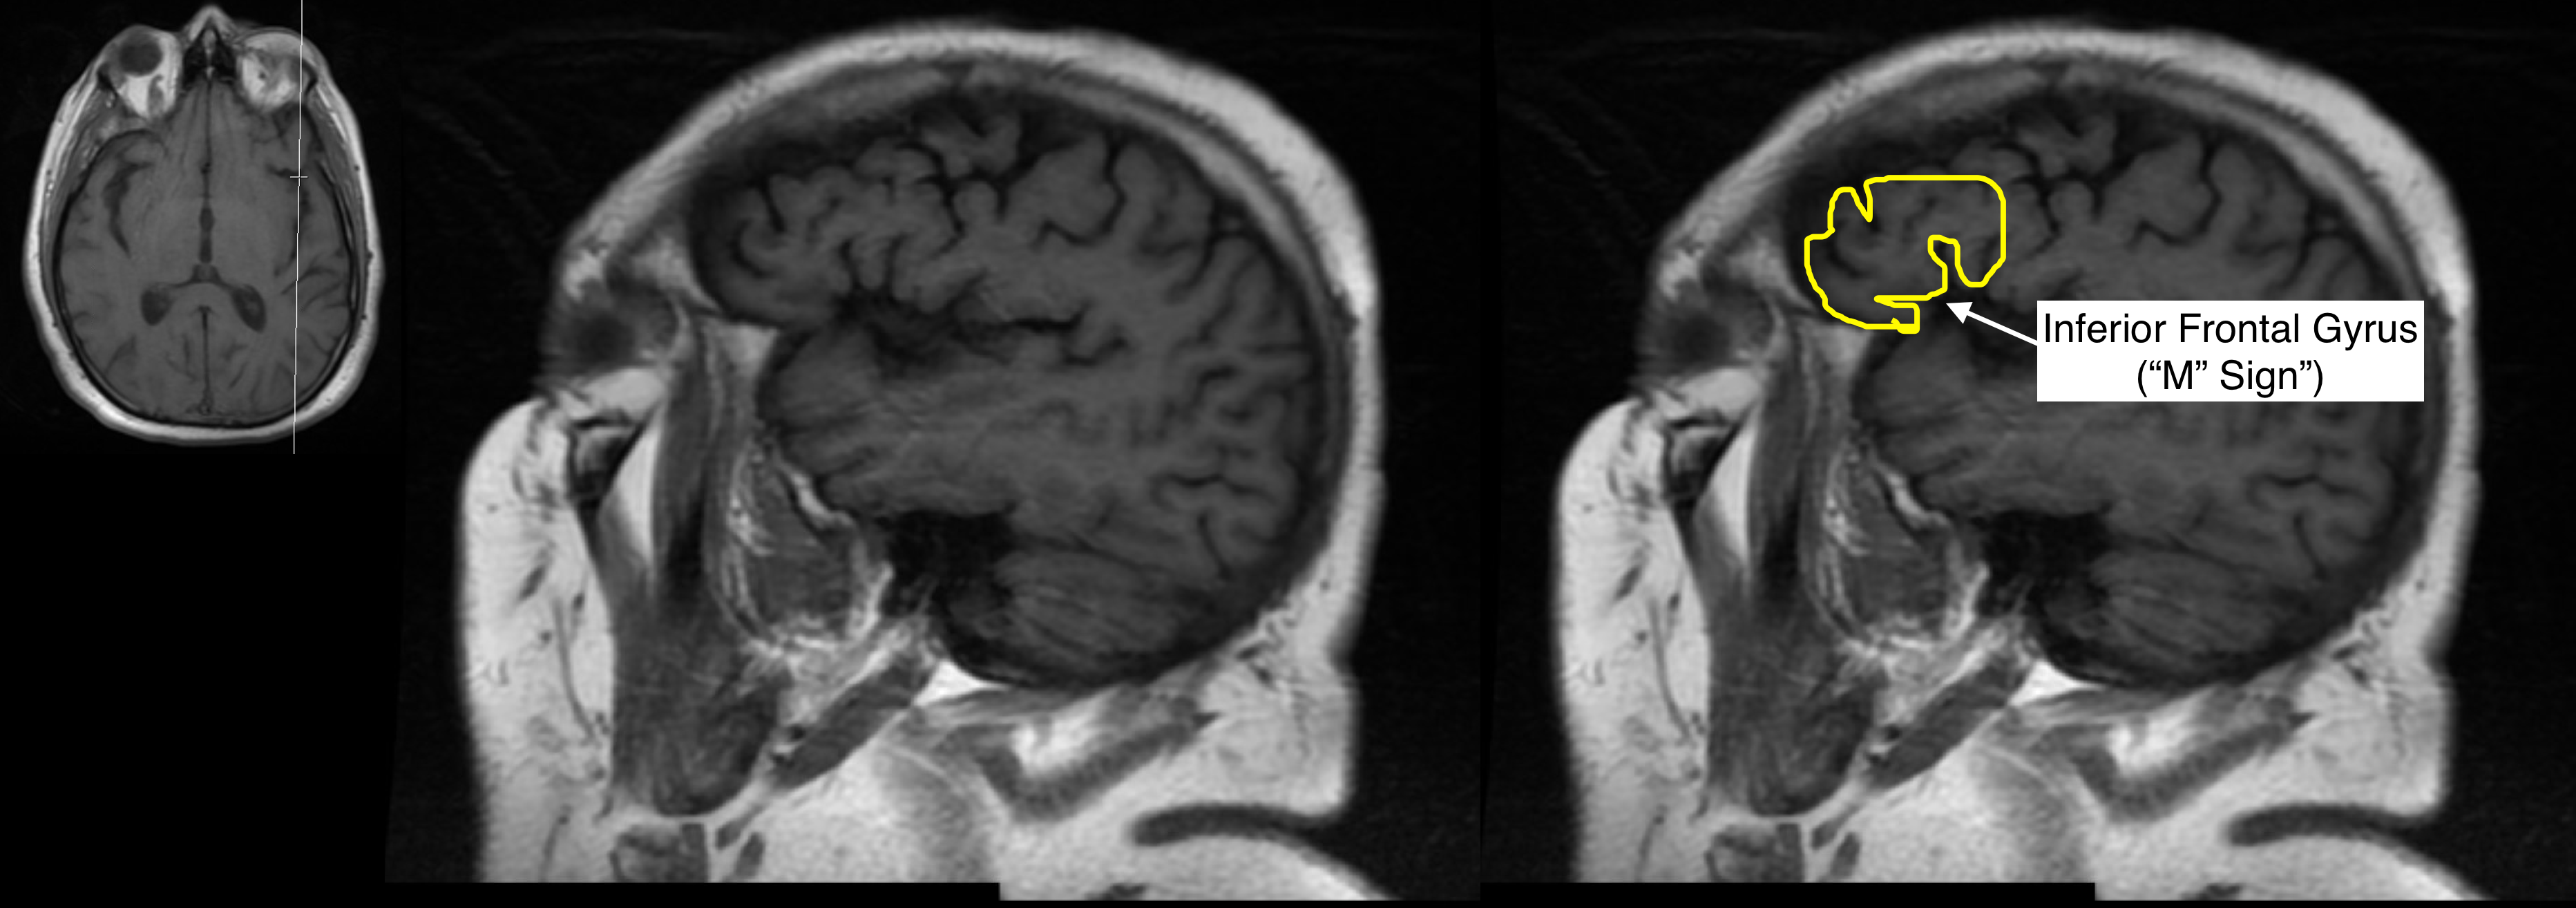

Radiological Anatomy Inferior Frontal Gyrus Stepwards Brain Gyrus Labeled Mri A review of brain magnetic resonance imaging (mri) is used as support. Brain mri with annotations of major structures. The anatomy of the brain is studied by means of axial, coronal and sagittal views. We shall also explore the anatomy of the 12 pairs of cranial nerves and anatomic variants without pathologic significance, relying mainly on. The main indications for. Brain Gyrus Labeled Mri.

Radiological Anatomy Inferior Frontal Gyrus Stepwards Brain Gyrus Labeled Mri Brain mri with annotations of major structures. The main indications for tailored. Specifically on the frontal cortex, we can. The anatomy of the brain is studied by means of axial, coronal and sagittal views. We shall also explore the anatomy of the 12 pairs of cranial nerves and anatomic variants without pathologic significance, relying mainly on. A review of brain. Brain Gyrus Labeled Mri.

Radiological Anatomy Inferior Frontal Gyrus Stepwards Brain Gyrus Labeled Mri The superior frontal gyrus is the medial most gyrus of the frontal lobe's superolateral surface, running from the frontal pole anteriorly,. Explore our video tutorial, quizzes, articles and labeled diagrams on this topic. Specifically on the frontal cortex, we can. Mri is the preferred imaging technique to assess hippocampal anatomy and pathology. The anatomy of the brain is studied by. Brain Gyrus Labeled Mri.